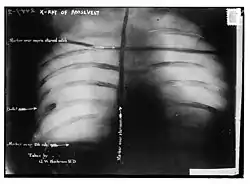

X-Ray of Schrank's bullet in Roosevelt's chest

Bullet lodged in Theodore Roosevelt's side

Afterwards, probes and an x-ray showed that the bullet had lodged in Roosevelt's chest muscle, but did not penetrate the pleura. Doctors concluded that it would be less dangerous to leave it in place than to attempt to remove it, probably remembering what had happened to Roosevelt's immediate predecessor who died after the bullet's wound got infected, and Roosevelt carried the bullet with him for the rest of his life.[16][17] In later years, when asked about the bullet inside him, Roosevelt would say, "I do not mind it any more than if it were in my waistcoat pocket."[18]